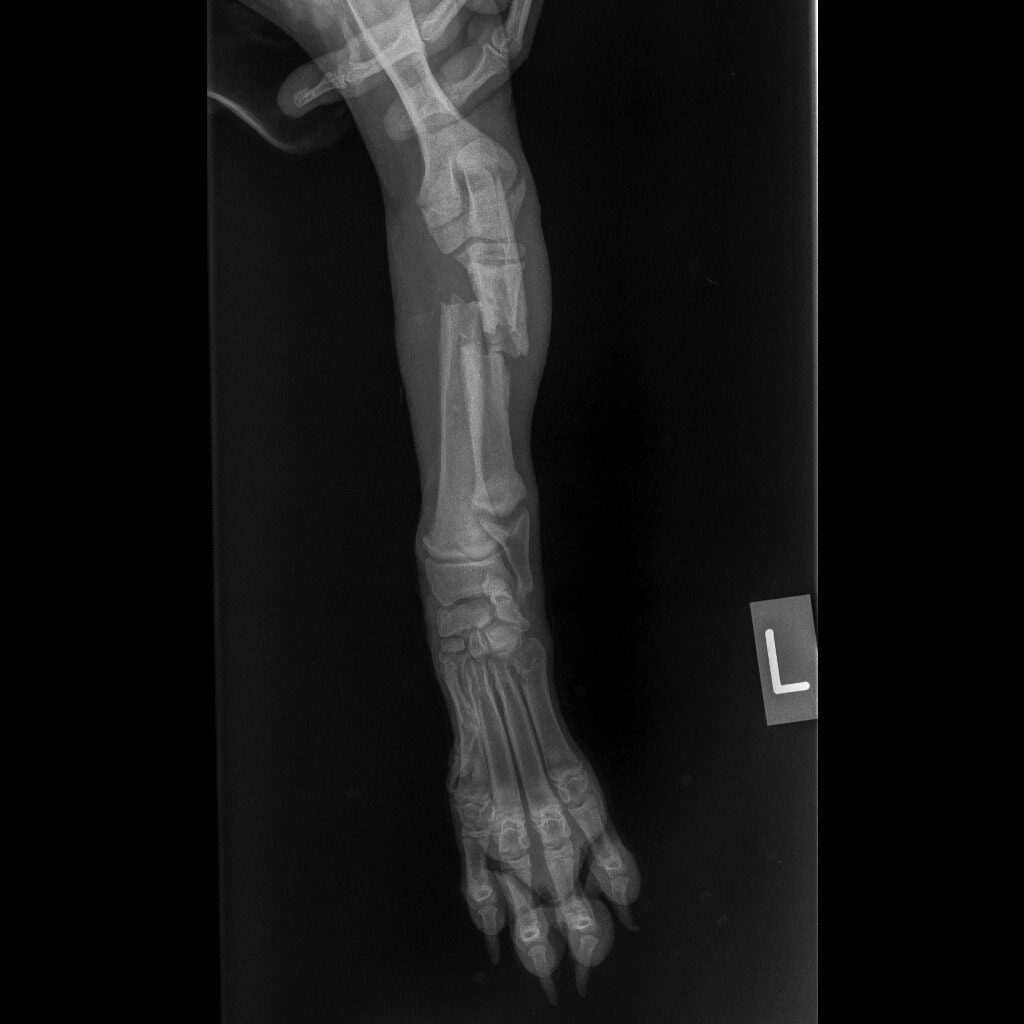

Ο Νικόλας βρέθηκε από εθελοντές και μεταφέρθηκε σε κτηνιατρείο. Δύο μπροστινά σπασμένα πόδια, πληγές, τσιμπούρια, ψύλλοι. Αυτή ήταν η κατάστασή του.

Η Maria Arkomani αναφέρει χαρακτηριστικά: «Δυστυχώς πολλοί ορθοπεδικοί έλειπαν και κάποιοι άλλοι δεν αναλάμβαναν το χειρουργείο του λόγω δυσκολίας και συγχρόνως επειδή είχαν περάσει μέρες από το σπάσιμο. Αμέσως πήγαμε στο κτηνιατρείο της Lena Kon για να δοθούν οι πρώτες βοήθειες από τον Νίκο Μαργαρίτη όπου τον ευχαριστούμε από καρδιάς. Βγήκαν ακτινογραφίες και έδειξαν τη ζημιά που είχε υποστεί αυτό το πλάσμα. Στο ένα πόδι μπήκε γύψος αλλά το άλλο ήθελε χειρουργείο. Στείλαμε σε πολλούς γιατρούς τις ακτινογραφίες αλλά οι απαντήσεις ήταν αρνητικές καθώς ήταν δύσκολο το χειρουργείο σε να κουτάβι με τέτοιο πρόβλημα. Ο μοναδικός γιατρός που μας απάντησε άμεσα και μπόρεσε να αναλάβει τον Νικόλα μας και να πάρει το ρίσκο του χειρουργείου είναι ο ορθοπεδικός Antonios Lionakis. Ένα χειρουργείο πάρα πολύ δύσκολο, με ρίσκο αλλά πρέπει να γίνει..»